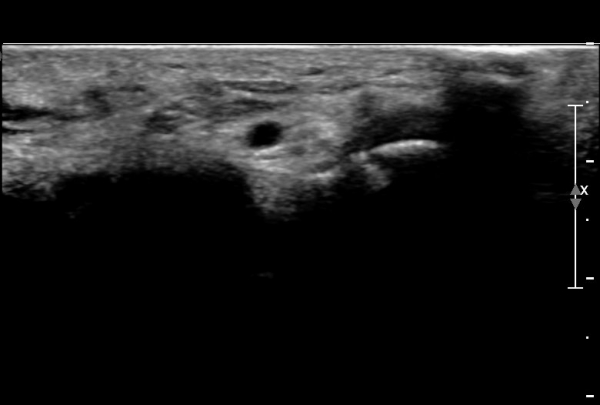

Á¶±Ý ´õ ¸»´ÜÀ¸·Î À̵¿ÇÏ´Ï Äá¾Ë»À ÇÇÁú°ñ ¿¬¼Ó¼º ¼Ò½ÇÀÌ °üÂûµÊ(»çÁö 3),

Äá¾Ë»À Á¾´Ü¸é°Ë»ç¿¡¼­ Äá¾Ë »À ±ÙÀ§ºÎÀÇ ÇÇÁú°ñ °ß¿­ÀÌ °üÂûµÊ(»çÁö 4).